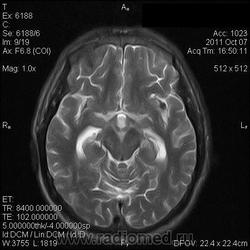

на МРТ - Определяется скопление крови в препонтинной цистерне, в проекции супраселлярной цистерны, в кортикальных бороздах полушарий головного мозга,  в проекции краниоспинального перехода. Выявляется горизонтальный уровень крови в задних рогах боковых желудочков. Боковые, третий желудочки резко расширены. Определяется перивентрикулярное повышение интенсивности сигнала от белого вещества головного мозга. Срединные структуры не смещены. Кортикальные борозды умеренно сглажены. Сильвиев водопровод прослеживается на всем протяжении. Отмечается смещение дна третьего желудочка каудально, с резким уменьшением размеров супраселлярной цистерны; базальные цистерны уменьшены в размере.

В проекции базальной артерии определяется аневризма размером до 4х6 мм.

Я не вижу участки скопления крови, а можно стрелочками указать, для особых не опытных ))) И аневризму стрелочкой пожалуйста. И все таки что за режим последней аксиальной? Tirm ( flair) ? Задние рога боковых желудочков мне не нравятся - но не ужели так кровь у вас видна ?

Мне напоминает FLAIR. В желудочках уровни крови и белое по субарахноидальным щелям тоже кровь. Аневризму тоже не вижу. Может долихоэктазия, если смотреть на сагитталы. Мелковато для меня, наверное.

Картинки действительно мелковаты. Я видел весь пакт изображений. Аневризма была хорошо видна на МР-ангиограммах, но Евгений их не выложил; а на обычных сканах ее четко не видно. Почему такие сигнальные характеристики у крови сложно сказать, я думаю, что в большую степень завязано давности кровоизлияния (четко не известно, когда оно произошло), на типе ИП и самом оборудовании... Такие вот мысли...